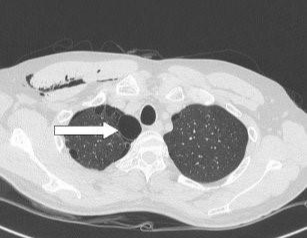

제가 본 학생은 신장(키)이 더 빠르게 생장하다 보면 폐 성장이 늦어지면서 그 빈 공간(흉막강)을 공기가 차게 되는 경우의 케이스였습니다. 폐와 흉각은 흉막이라는 막에 쌓여 있는데, 평소에는 공기 대신 흉막액이 있어야할 공간인 곳이죠. (자발성 기흉.)

- 일차성 자연기흉 : 기존에 폐질환이 없는 건강한 사람에서 발생한 기흉 (키가 크고 마른 사람, 흡연, 대기오염)